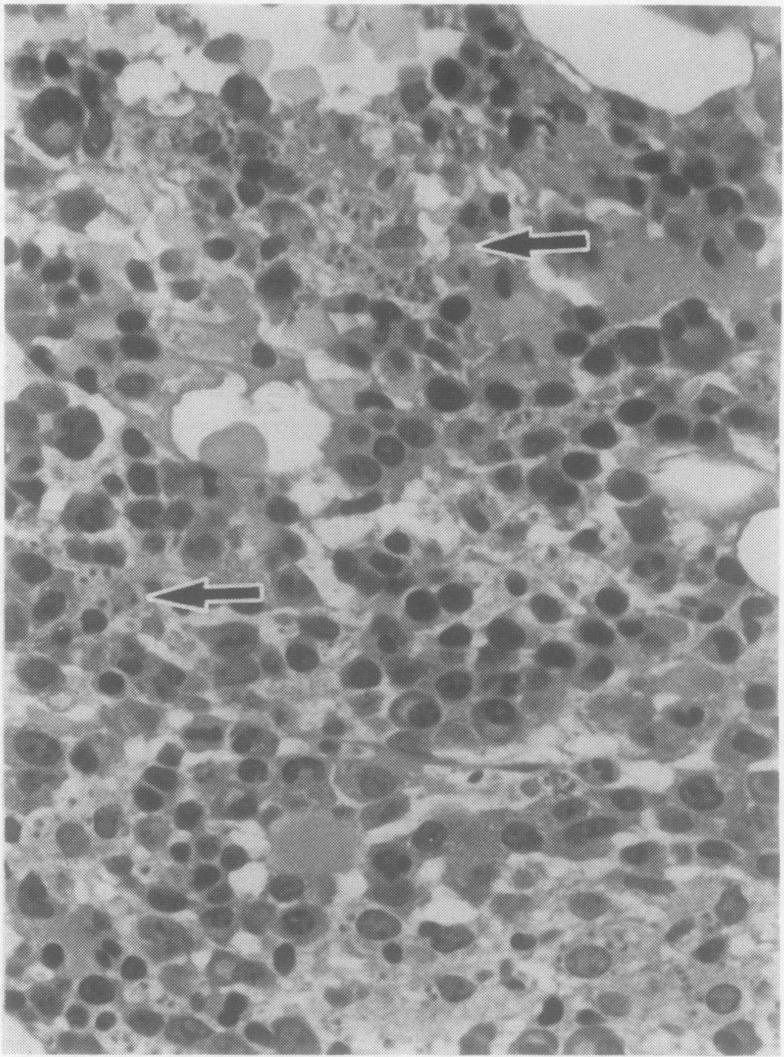

Opportunistic protozoan infections in human immunodeficiency virus disease: review highlighting diagnostic and therapeutic aspects.

摘要